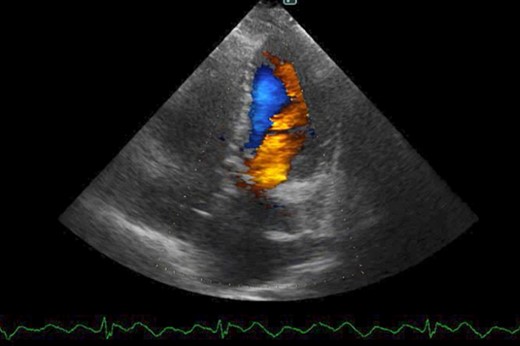

The patient was followed up as an outpatient since 2010 for incomplete AVSD and congestive heart failure by the Cardiovascular Surgery Department at our hospital. She did not wish to undergo surgery; therefore, we continued to follow her as an outpatient. Mitral regurgitation (MR) III-IV and mitral valve deviation was detected by echocardiography at approximately 2022, with worsening heart failure symptoms (New York Heart Association (NYHA) class III status). Echocardiography revealed an ejection fraction (EF) of 65%; severe MR; mean pulmonary artery pressure (PAP) of 32 mmHg; left-to-right shunt flow; left ventricular dysfunction (LVDd) of 48 mm; LVDs, 32 mm; and cleft mitral valve (Fig. 1). Chest radiography revealed a cardiothoracic ratio (CTR) of 58% and a costophrenic angle (CPA) sharp (Fig. 2). Cardiac catheterization revealed a Qp/Qs ratio of 2.6. Therefore, we performed a mitral valve repair and patch closure of the primum ostium defect.

Preoperative cardio echography showing fraction EF 65%, MR severe, mean PAP 32 mmHg, left-to-right shunt flow, LVDd 48 mm, LVDs 32 mm, and a cleft mitral valve.